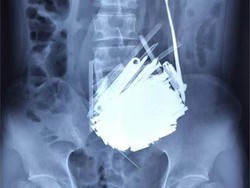

Ratusan Benda Asing Berada dalam Perut Pria 39 Tahun di China

Dokter di China temukan 120 benda asing dalam perut pasien skizofrenia. Operasi berhasil, pasien stabil dan dirujuk untuk perawatan psikiatri lanjutan.